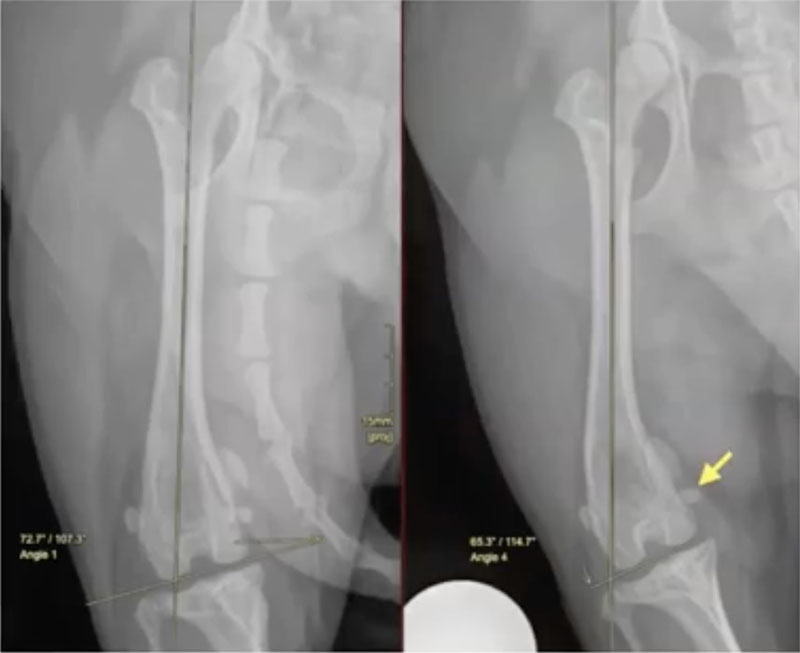

In Figure 5 (8:37) is another example. Same dog, same leg, very similar position, but in the right-hand image there's slight rotation. The fabellae are not symmetrically bisected, and this shows a 7 positioning error. which would lead to the wrong decision on treatment. So correct positioning is critical when measuring aLDFA from radiographs. It's certainly much easier to measure the correct angle if you have access to CT because you can manipulate the image to get the bone in the right plane after acquisition of the scan, so positioning is less critical.